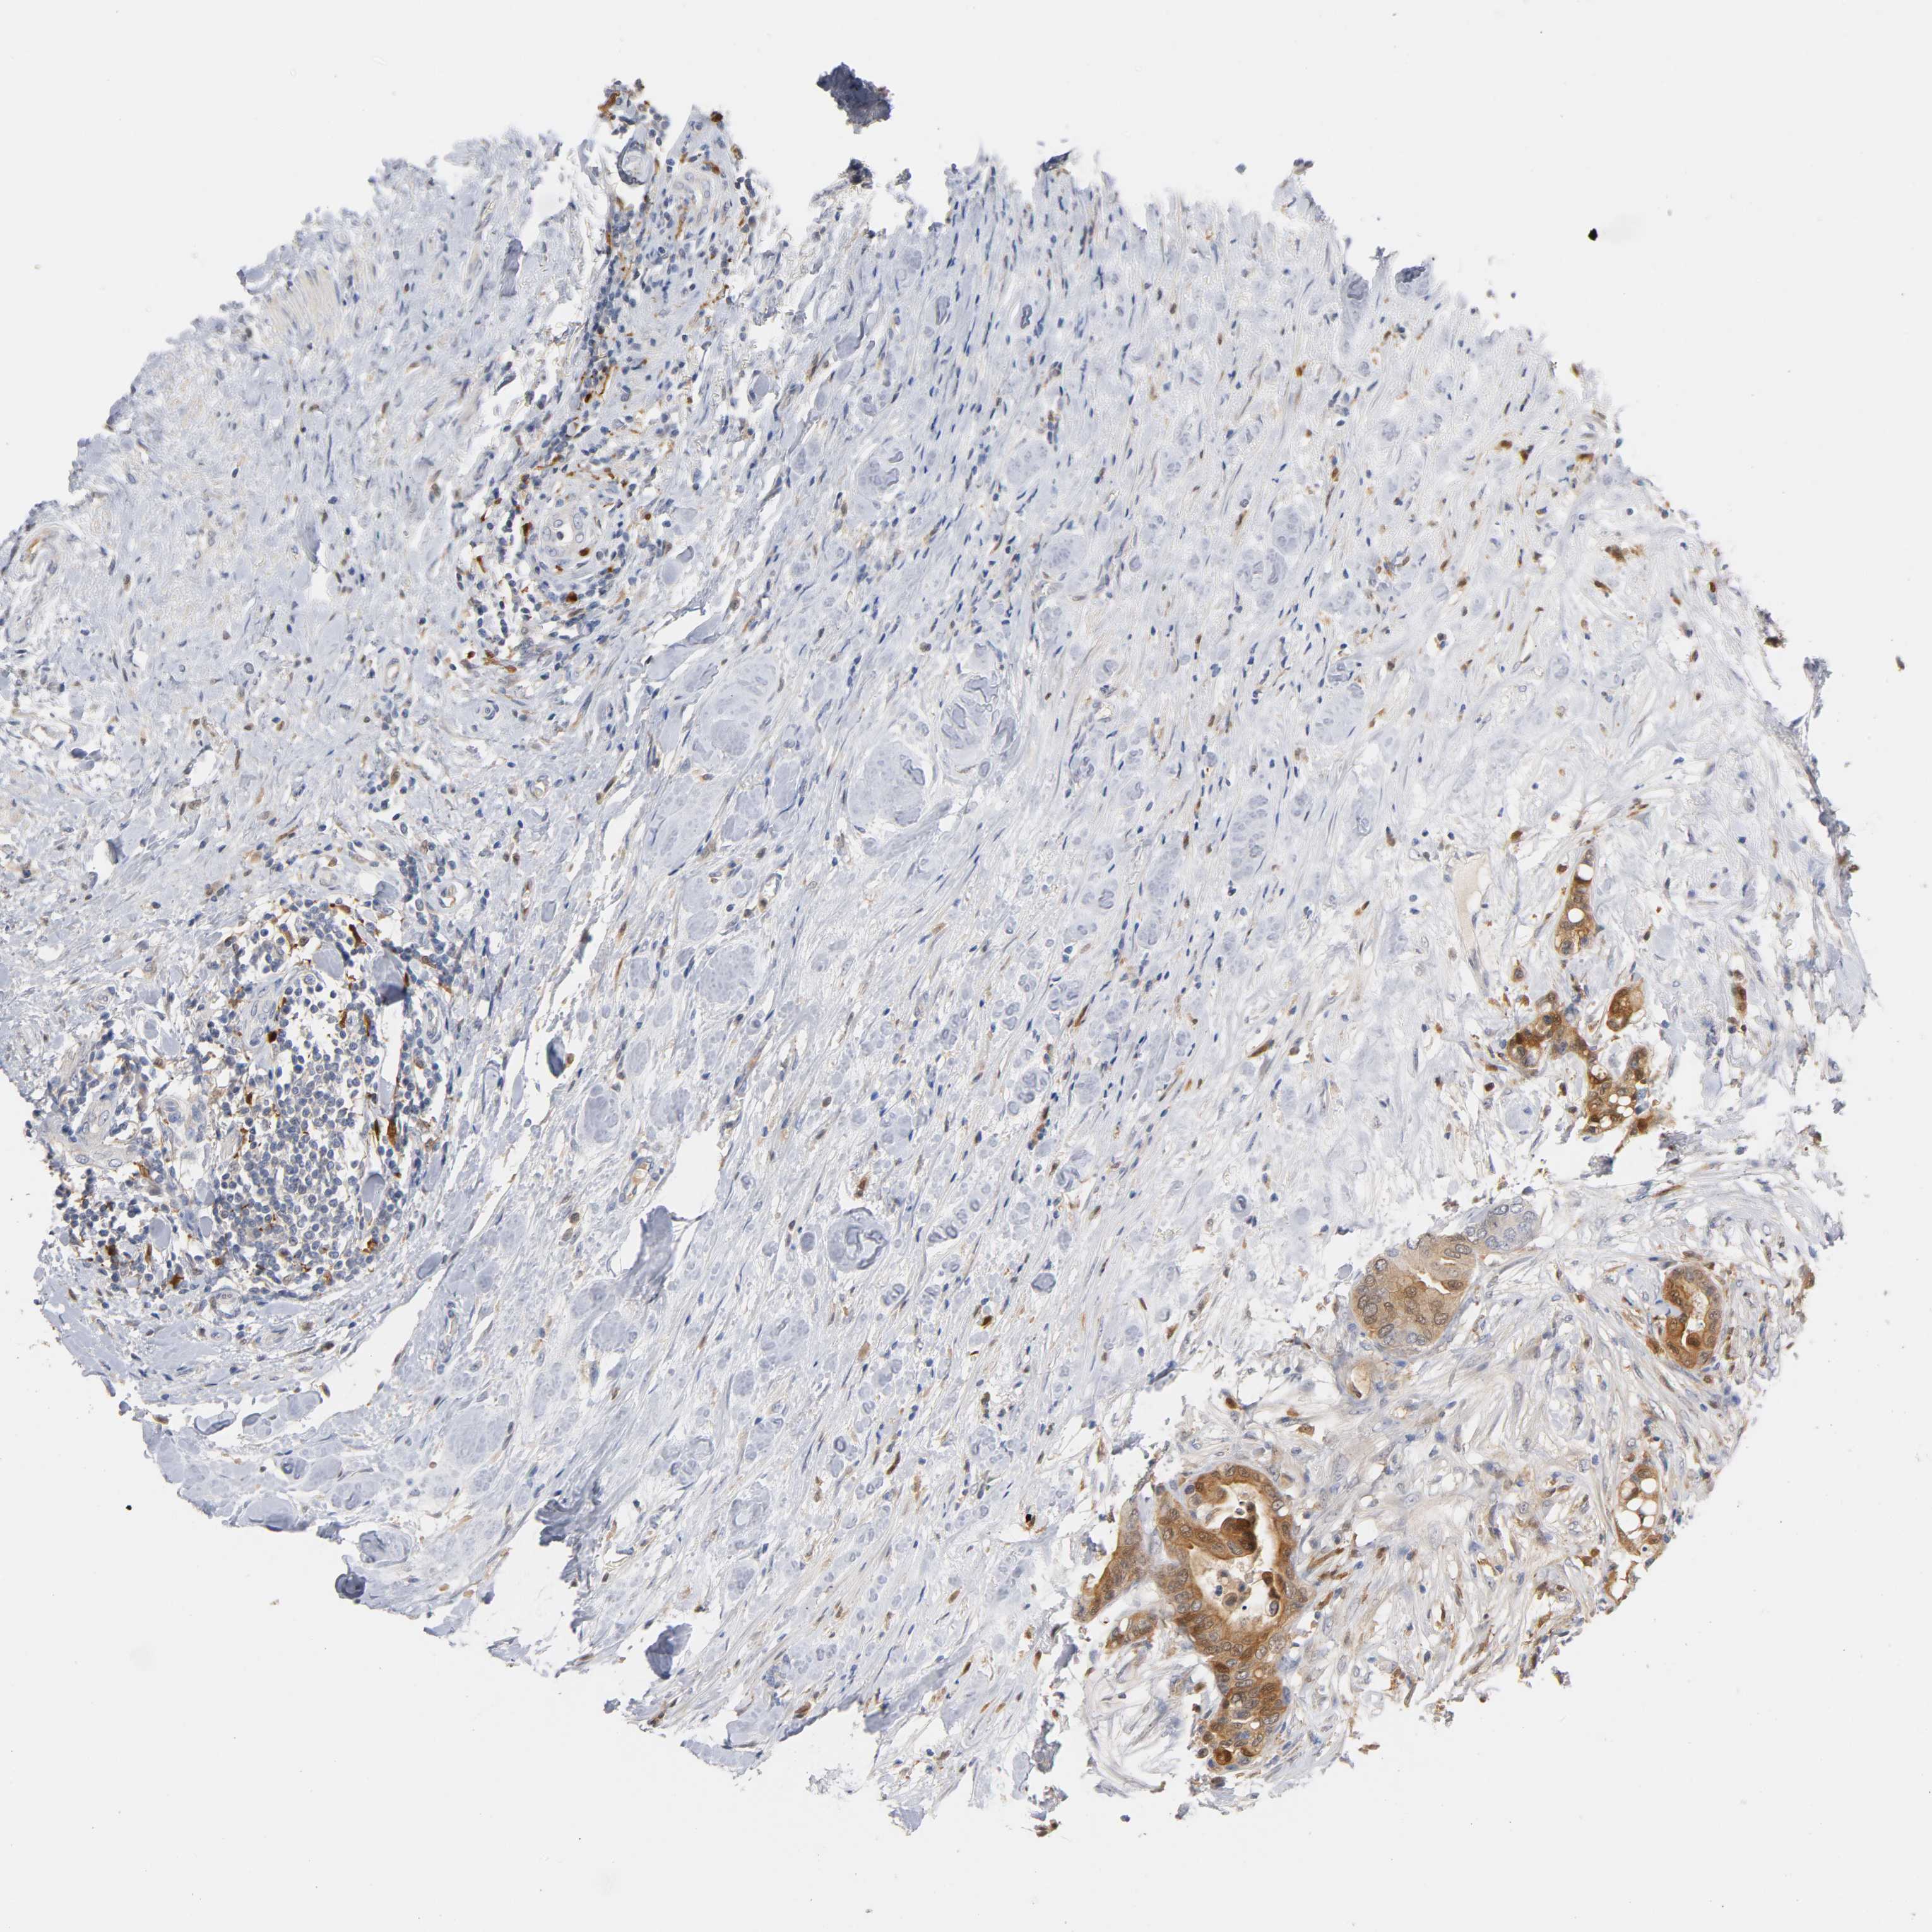

CANCER COLORECTAL CANCER Show tissue menu

Colorectal cancer

Human cancer